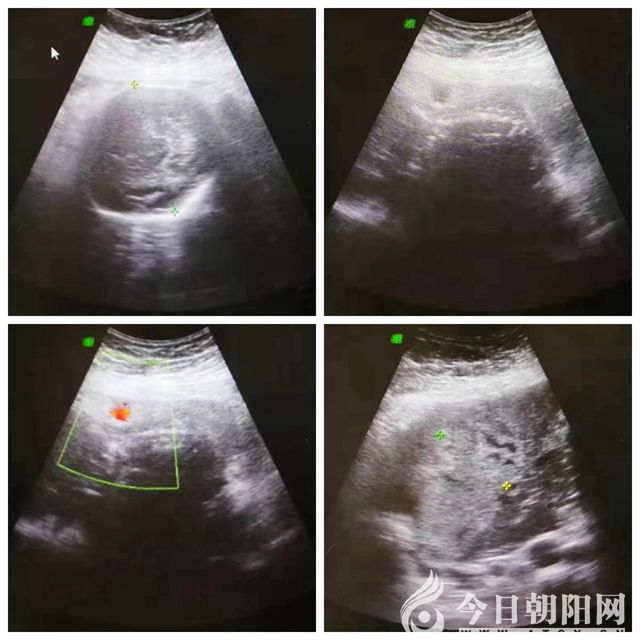

8月7日下午4時(shí)10分,家住朝陽市雙塔區(qū)的王女士因“停經(jīng)7個(gè)月、不規(guī)律腹痛1天”來到市二院就醫(yī)。外地超聲懷疑腹腔妊娠,乘車從錦州返回朝陽就診。產(chǎn)科一病房接診醫(yī)生詢問病情后,立即匯報(bào)科主任,科主任緊急請(qǐng)示院領(lǐng)導(dǎo)。王憲珍副院長得知情況后,迅速組織婦產(chǎn)科主任孫鳳華、產(chǎn)科一病房主任白麗萍、超聲科主任張華杰等人員到超聲科進(jìn)行全院會(huì)診,簡單詢問病史及查體后當(dāng)即診斷為:妊娠30周零6天、瘢痕子宮、子宮破裂。由于病情危重,腹腔內(nèi)多量積血,目前胎兒尚存活,需即刻手術(shù),否則將危及母嬰兩條生命。在此緊急情況下,醫(yī)院立即開通綠色通道,啟動(dòng)危重孕產(chǎn)婦搶救預(yù)案,通知檢驗(yàn)科、手術(shù)室、輸血科、麻醉科、新生兒科等科室迅速做好術(shù)前準(zhǔn)備,短短數(shù)分鐘就把患者從超聲科直接推入手術(shù)室。

在全麻下,迅速開腹腔,術(shù)中見盆腹腔積血及血塊約1500毫升,胎兒此時(shí)游離于大量血液之中,快速于腹腔中取出一女活嬰,新生兒輕度窒息,斷臍后交臺(tái)下處置。探查見患者子宮右側(cè)宮角增大約15x10厘米,表面紫藍(lán)色,見破裂口長約6厘米,多量活動(dòng)性出血,整個(gè)胎盤植入于右側(cè)宮角,向患者家屬交代病情,行部分子宮切除術(shù)及子宮成形術(shù)。術(shù)中輸紅細(xì)胞4單位、血漿400毫升。一切都在緊張有序中進(jìn)行,此時(shí)的手術(shù)室就像一個(gè)沒有硝煙的戰(zhàn)場,大家鼓足了勁,拼命和死神賽跑。